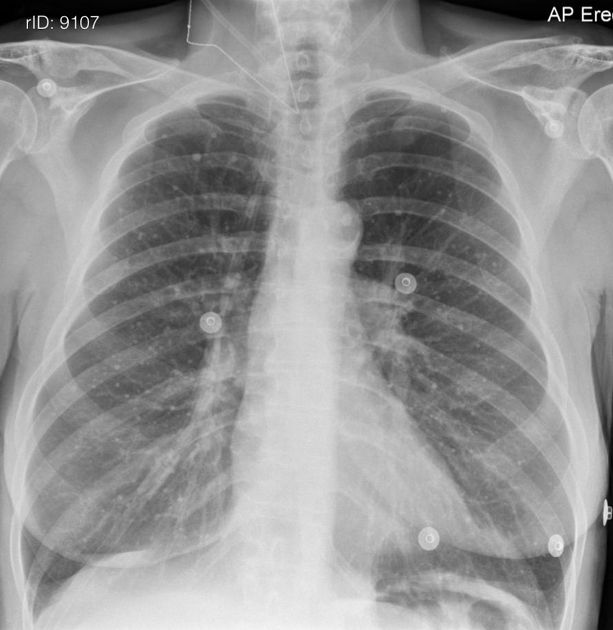

결핵(Tuberculosis, TB)은 Mycobacterium tuberculosis라는 박테리아에 의해 발생하는 전염병입니다. 결핵은 주로 폐에 영향을 주지만, 다른 부위에도 영향을 미칠 수 있습니다. 아래는 결핵의 주요 증상에 대한 설명입니다.

이러한 세균 감염은 대개 폐에서 발생하지만, 다른 부위에도 영향을 줄 수 있습니다. 결핵은 대개 폐에 집중되어 "폐결핵"이라고도 불리며, 폐 이외의 부위에 생기는 경우도 있습니다. 박테리아가 폐 이외의 장기에 감염되는 경우는 "부속기관 결핵"이라고도 불립니다.